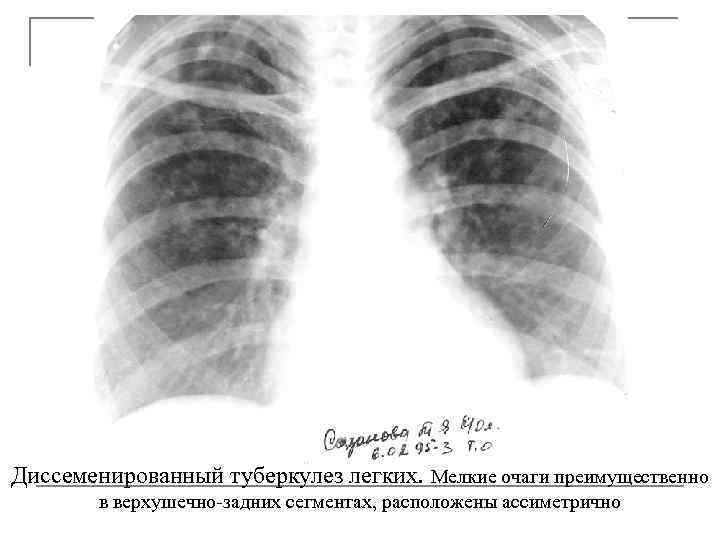

Диссеменированный туберкулез легких. Мелкие очаги преимущественно в верхушечно-задних сегментах, расположены ассиметрично

Подострые гематогенные диссеминации q асимметрия расположения очагов и зон поражения q преимущественное поражение верхушечно-задних сегментов q очаги множественные однотипные или полиморфные q наличие тонкостенных каверн q усиление легочного рисунка по типу лимфангита q в 5 -6% встречается преимущественно каудальное или базальное расположение очагов, что вызывает значительные трудности в диф. диагностике q нередко наблюдается эксудативный плеврит, который быстро рассасывается, а иногда является первым Рсимптомом заболевания